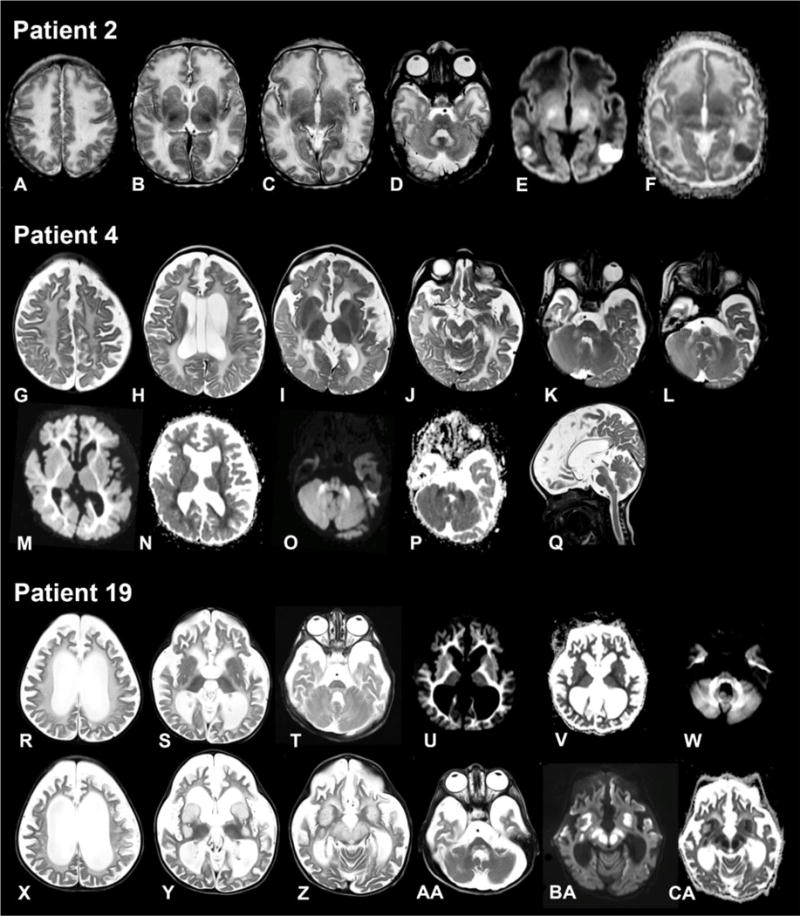

Fig. 3. Magnetic resonance imaging of the brain from patient 2 (4 days), patient 4 (9 months) and patient 19 (3 years).

Patient 2 (age 4 days). Axial T2-weighted images (A–D) show swollen and slightly hyperintense aspect of supratentorial white matter. There are several defects in the basal ganglia (B). There are two small areas at the parietooccipital border on both sides where the cortex is less well defined (C) with corresponding impaired diffusion (E) and decreased apparent diffusion coefficient (ADC) (F). Signal of the dorsal tegmental tracts and hilus of the dentate nucleus is increased (D). In the supratentorial white matter, diffusivity is increased (E) with elevated ADC (F), with exception of the posterior limb of the internal capsule.

Patient 4 (age 9 months). Axial T2-weighted images (G–L) demonstrate global supratentorial atrophy, a cavum vergae and a left paraventricular cyst (H) and a mild diffuse increase of the supratentorial white matter signal (G–I). The tectum (J), pyramidal tracts, dorsal tegmentum (K) and middle cerebellar peduncles (K, L) have an elevated signal. Diffusion is impaired with decreased ADC in the supratentorial white matter (M, N) and the middle cerebellar peduncles, dorsal tegmental tracts and pyramidal tracts (O, P). The sagittal T2-weighted image (Q) shows normal volume of the cerebellum.

Patient 19 aged 3 years (R–W) and 2.5 months later (X-CA). Severe supratentorial atrophy is evident on the axial T2-weighted images (R–T), with now also thinning of the brain stem (T). White matter signal is diffusely elevated (R–T) with impaired diffusion (U, W) and a corresponding low ADC (V). 2.5 months later, basal ganglia (Y), substantia nigra and red nucleus (Z) are grossly swollen and hyperintense with corresponding impaired diffusion (BA) and ADC (CA). Also the dorsal tegmental tracts are swollen (AA).

In six children, imaging had been performed in the chronic phase of the disease, between age 3.5 months and 5 years. (Figure 3g–q). Supratentorial atrophy was prominent in four individuals and already present at age 3.5 months. The brain stem was hypotrophic in three patients. Pericerebellar spaces were prominent in five children. The white matter signal was diffusely elevated on the T2-weighted images with restricted diffusion in some patients. Myelination was severely delayed also on the T1-weighted images. Basal ganglia lesions were present in three cases.

In three children, imaging showed acute changes (Fig. 3x–ca). In two, basal ganglia and mesencephalon were swollen and their T2-signal of the basal ganglia was inhomogenously elevated with restricted diffusion. Signal abnormalities and diffusion restriction of the dorsal tegmental tracts were more prominent than in the chronic phase. One child had in addition increased T2 signal and impaired diffusion in both medial thalami and the cervical central spinal cord (not shown). In one child, the oldest of this series, at the age of 11 years there was evidence of an old stroke-like episode involving the right parietal and occipital lobes with cortical haemorrhagic necrosis and a new lesion with impaired diffusion of the left parietooccipital cortex. Clinically she presented with left- sided spastic hemiparesis. This child also had old defects in the basal ganglia and a partly destructed cerebellum.

Brain imaging shows non-specific findings with increased water content of the white matter and rather large but non- specific germinolytic periventricular cysts in neonates. Severe atrophy ensues quickly, and decreased apparent diffusion coefficient (ADC) in the affected white matter suggests intramyelinic oedema. In some patients, central grey matter structures including the mesencephalon show increased volume and T2 signal and decreased ADC, as in other mitochondrial disorders, indicating acute energy failure.